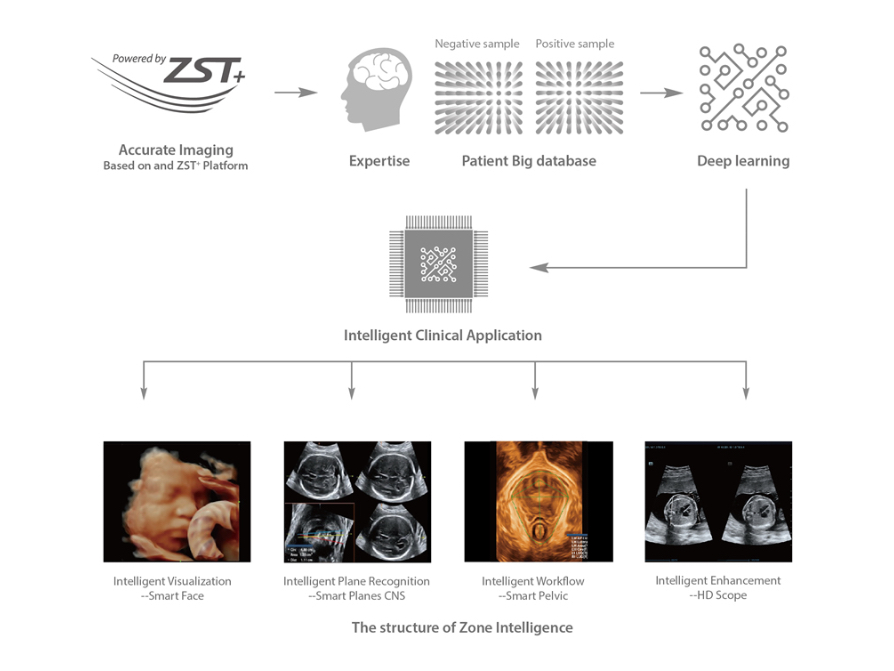

Powered by the channel data based ZST+ platform, the new Resona series with Zone Intelligence builds up a truly smart mechanism to deliver a new level of intelligence. The core of Zone Intelligence is deep learning that is based on big data base and Ultrasound expertise. As a result, it is able to provide multiple intelligent retrospective processing, leading to efficient and effective image visualization, plane recognition, measurement, and image enhancement.